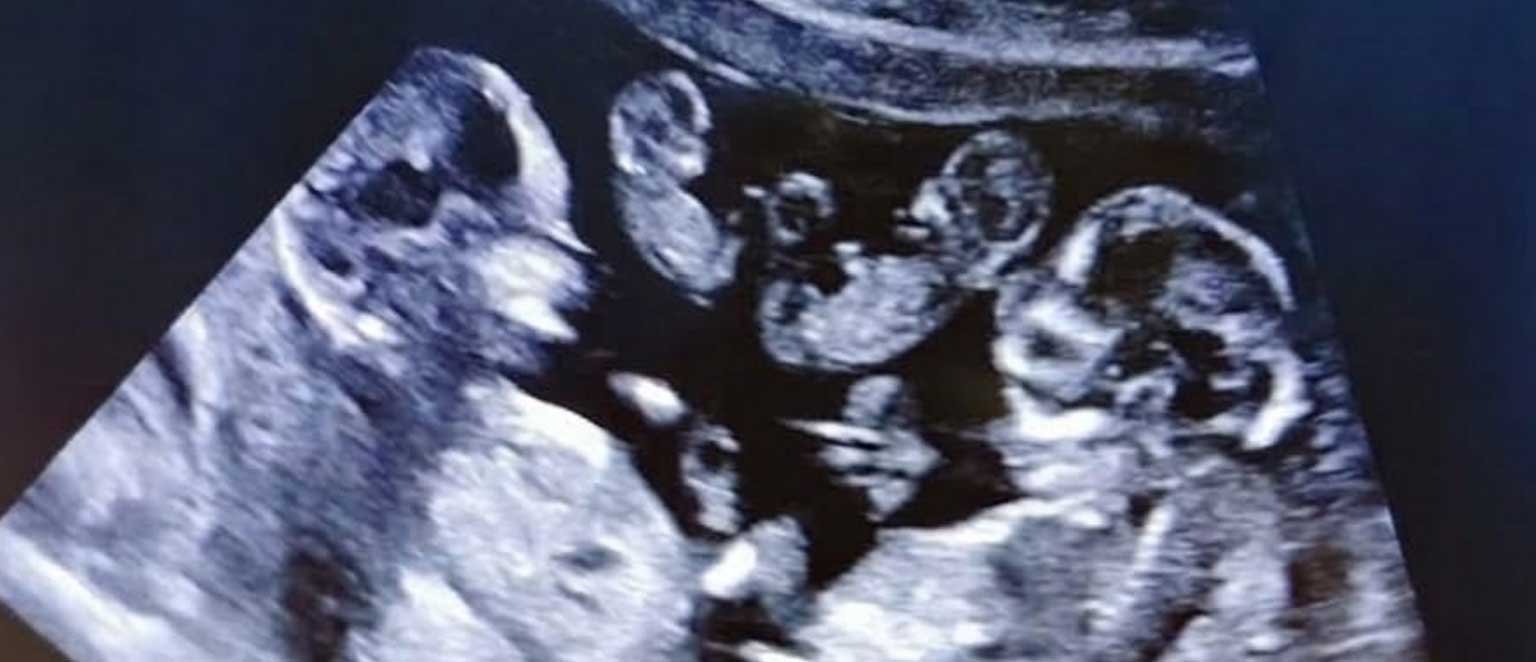

وتداول عدد من مستخدمي مواقع التواصل الاجتماعي مقطع فيديو يُظهر طبيب نساء وتوليد أثناء الكشف على السيدة باستخدام جهاز السونار، حيث أوضح وجود ثمانية أجنة داخل الرحم، في واقعة وصفها الأطباء بأنها من الحالات النادرة للغاية.

وأوضح الطبيب أن الحالة خضعت لفترة من المتابعة والعلاج الدقيق، وكانت المفاجأة أن الحمل حدث بشكل طبيعي دون تنشيط أو حقن مجهري، ليتم اكتشاف وجود 8 توائم داخل الرحم خلال الفحص الطبي.